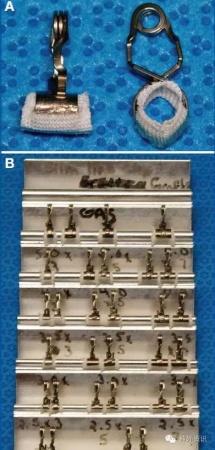

Sundt Clip Graft(“救命夹”)

50年前,美国医学圣地Mayo Clinic的神经外科医生Thoralf Sundt发明了一套神经外科血管夹,目的是为了治疗术中颅内动脉意外损伤撕裂以及梭形的夹层动脉瘤。随着科技的进步,神经介入长足进展,越来越多夹层动脉瘤可以通过介入的手段来完美解决,但不仅Mayo Clinic,Spetzler、Lawton、Juha这些神经外科**的手术室都始终备着一套Sundt Clip Graft(见图10),为的就是一旦发生术中的颅内动脉意外损伤,Sundt Clip Graft可以“救命”。

图10. Sundt Clip Graft。

Sundt Clip Graft的构成很简单,金属部分设计理念有点像平时家庭晒被子时用的夹子,夹子里填充的是teflon,也就是三叉神经微血管减压术中用的垫片。Sundt Clip Graft分成各种型号,以配备不同的颅内动脉。一般情况颈内动脉需要内径5-6mm的Sundt Clip Graft,大脑中大脑前大脑后动脉需要内径2.5mm的Sundt Clip Graft。

Sundt Clip Graft的优点在于:通过金属弹簧夹,可给予动脉壁持续定点的压迫力,通过teflon更有效止血;

再狭窄率比较低,最大单中心使用报道是Mayo Clinic,20年17例,其中,14例通畅率在80%以上,1例闭塞,1例狭窄50%,1例无随访;

在很多特殊情况下,比如深部血管的破裂、照明及操作角度都不理想,予以血管吻合困难极大;而一些肿瘤包绕的血管术中撕裂,它的撕裂口常不规则,对于不规则的破口予以血管吻合,基本是不可能的,因此Sundt Clip Graft可能是唯一方案。

体积较大,比较笨拙,容易和周边的临时阻断夹“打架”;

很可能牺牲小的穿支血管,比如此例手术,在予以放置Sundt Clip Graft后需反复调整,尽量靠近前床突,即使牺牲后交通动脉,也争取保留脉络膜前动脉。

随着神经介入的长足进步,曾经一些脑血管病的传统治疗办**在逐渐较少,像Sundt Clip Graft,50年前的发明者使用目的更多是为了夹层动脉瘤和血泡样动脉瘤,现在神经介入技术提供了更好的办法。但在显微神经外科高度发展的今天,术中的大血管损伤仍会非常偶然的发生。临时血管搭桥固然是一种解决手段,但Sundt Clip Graft却能在保持动脉通畅的前提,立刻的止血,提供赶紧的术野,稳定术者的信心;我们称之为“救命夹”并不为过。